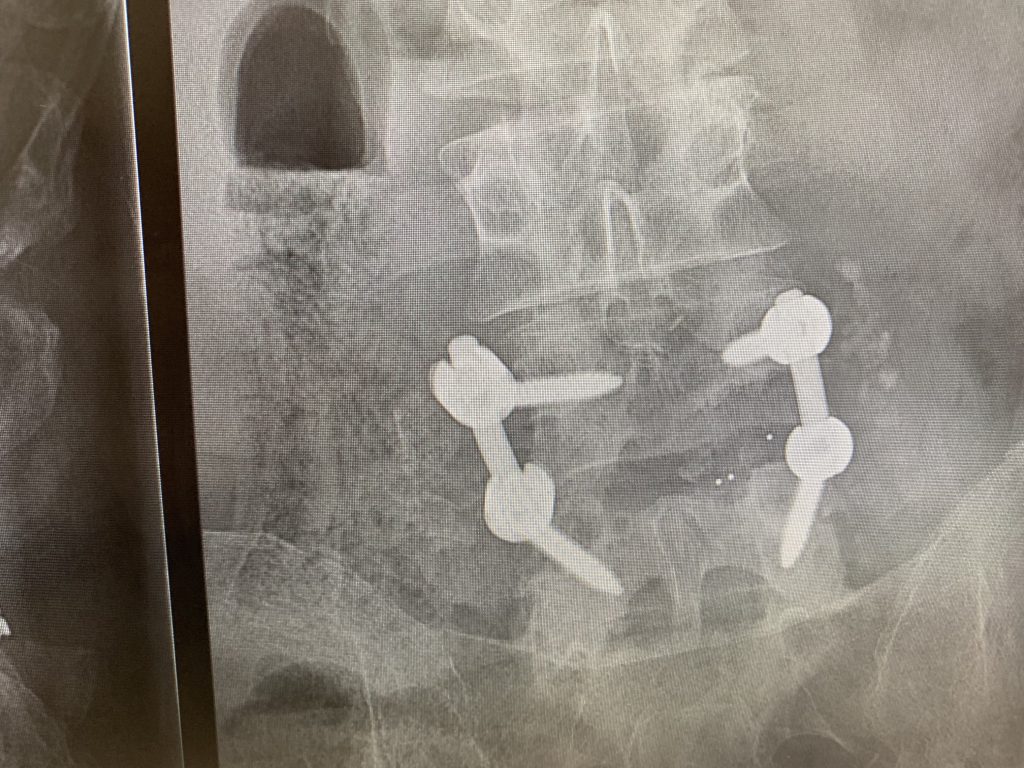

After many years of chronic back pain and nerve discomfort in my legs and many attempts at a remedy, I was introduced to Dr. Todd Albert and his fabulous Team in late July of 2019. He was confident he had a solution for me: a TLIF and additionally a laminotomy and disc decompression in other areas. Within 9 days I was in the operating room and on the road to recovery. Dr. Albert explained the procedure clearly and was very comforting to me and my family in the aftermath. The care I received in my 5 days at HSS was superb.